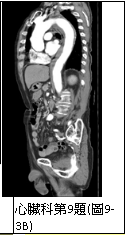

9. 男性病人,72歲,因尖銳性上背部疼痛突然發作,同時伴有急促呼吸及眩暈,乃往急診求治。時,血壓149/91 mmHg;心跳,70/min; RR, 20/min;其他理學檢查並無任何異常。病人每天抽煙一包,已有五十多年。Chest X-ray、ECG及CT,如圖9-1、圖9-2、圖9-3A及圖9-3B後,及其初步處置,後轉送加護病房途中,又突發後背疼,同時雙腳麻及疼痛,並呈現雙腳發紺,乃急照另次CT如圖9-4所示。請問下列何者決策不恰當? (A) 控制心收縮血壓在100-120 mmHg及心跳60-80/min (B) 靜脈注射Labetalol 30 mg/min (C) 口服Propranolol 20 mg tid po (D)口服Aspirin 100 mg qd 及Clopidogrel 75 mg qd (E) 外科會診,緊急手術